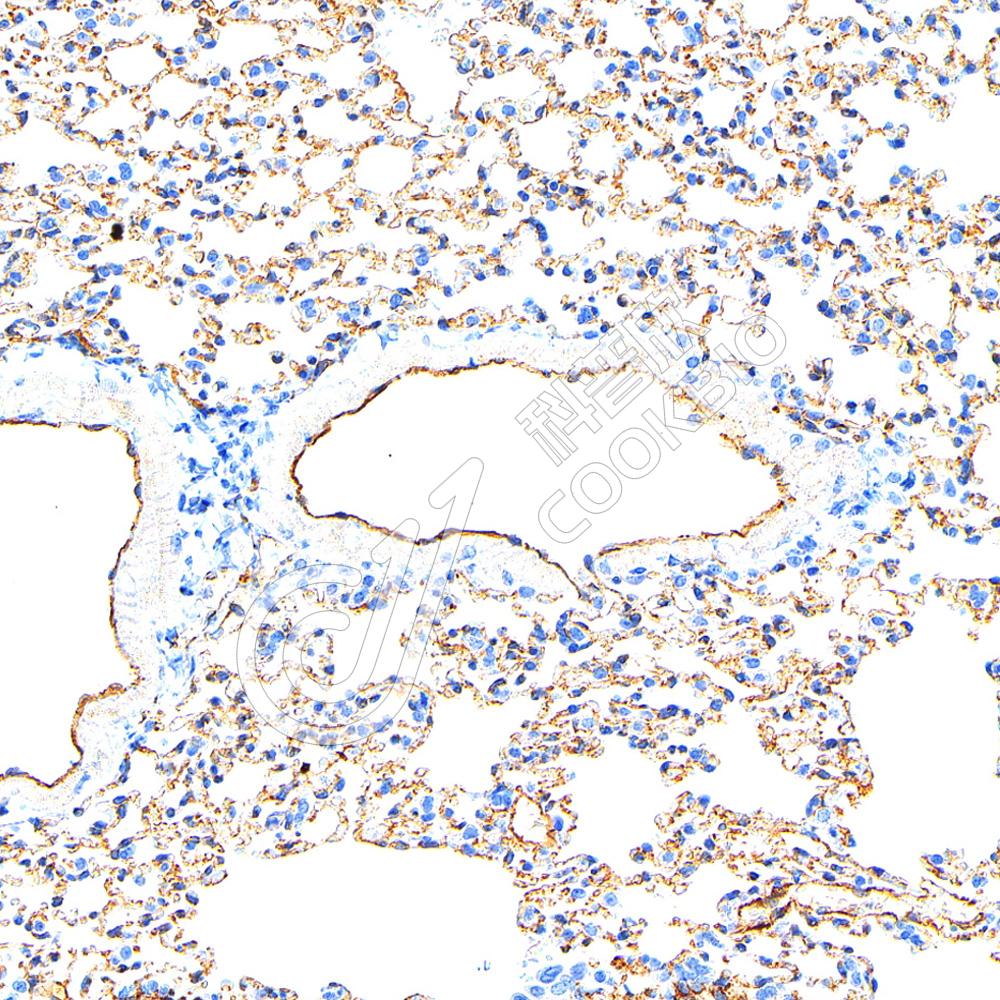

IHC检测CD31蛋白(货号 K2360015).

样品: 小鼠肺, 4%多聚甲醛 (货号KSG1101) 固定12-24小时.

抗原修复: 柠檬酸抗原修复液(干粉, pH 6.0) (KSG1201), 高压锅均匀喷气计时2分钟.

—抗: 1: 800稀释, 4℃ 孵育过夜.

二抗: S-vision免疫组化多聚二抗(山羊抗小鼠), 即用型(货号KB3903), 室温孵育20分钟.

样品: 大鼠肺, 4%多聚甲醛 (货号KSG1101) 固定12-24小时.